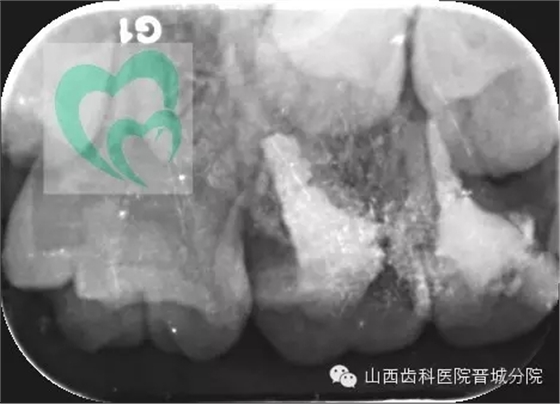

下面展示一例由我院龐超醫(yī)生操作并整理資料的兒童乳牙預(yù)成冠病例。